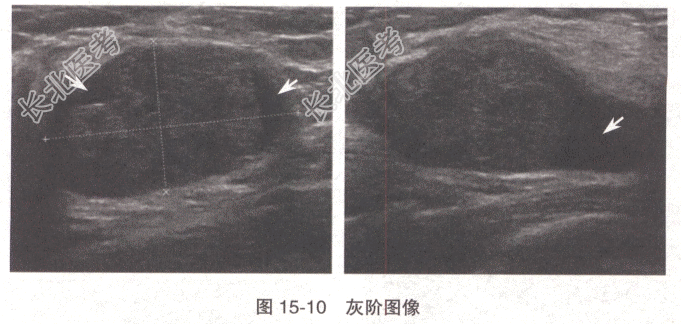

- 单项选择题患者,女性, 40岁。洗澡时偶尔发现左乳上方包块就诊,查体发现左乳上方触及一质地中等的包块(图15-10)。诊断应首先排除

A、乳腺增生结节

B、乳腺囊肿

C、乳腺脓肿

D、乳腺纤维腺瘤

E、乳腺恶性肿瘤